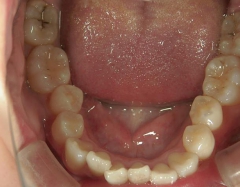

矯正歯科 治療後矯正歯科 プチワイヤー矯正 治療後矯正歯科(プチワイヤー矯正)治療後

矯正歯科 治療後

矯正_灰色.pngno.8_8495_治療後_下.jpg矯正_灰色.png